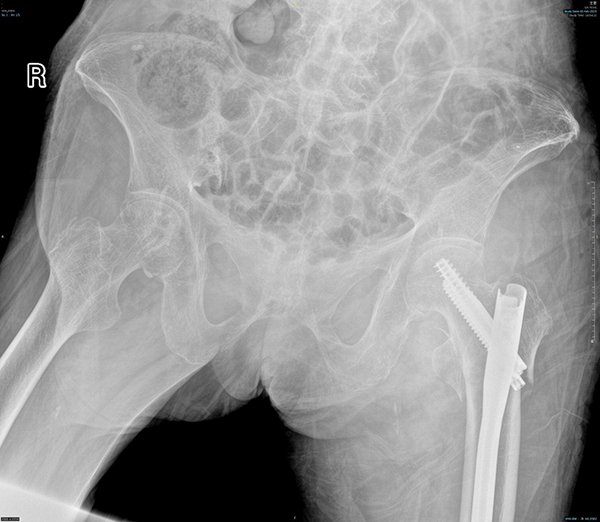

创伤中心主任医师王伯珉、王大伟医疗团队对李奶奶的身体状况进行了全面而细致地评估,制定了详细且个性化的手术方案,并同患者家属进行了充分的沟通。考虑到高龄患者的身体耐受性,手术团队精心选择了微创手术方式,以期最大限度减少手术创伤和术后并发症的发生。在麻醉手术科团队的紧密配合下,手术过程顺利,李奶奶的骨折得到了精准修复。

术后,创伤中心医护人员以高度的责任心和专业的护理技能,为李奶奶提供了精心护理。在医护人员的悉心照料下,李奶奶恢复良好,很快便下地行走并顺利出院。李奶奶的家属对医院创伤中心的医疗团队表达了深深的感激之情。